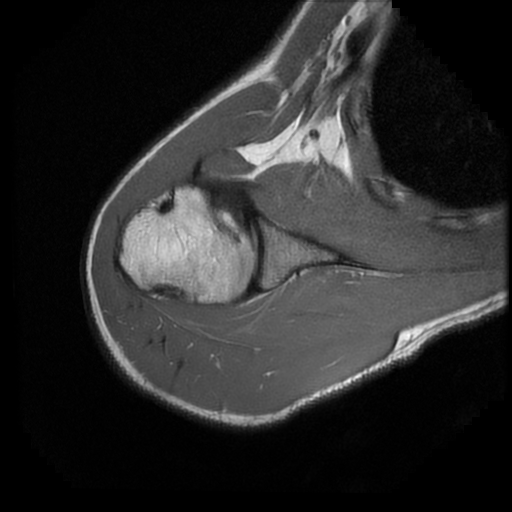

TECNICA EMPLEADA

Se coloca al paciente en decúbito supino, utilizando bobina dedicada de 8 canales, obteniendo imágenes en planos axial, sagital y coronal, secuencias, Spin Echo, Eco de Gradiente, potenciadas a Densidad de Protones, con pulsos de saturación de grasa.

HALLAZGOS IMAGENOLOGICOS

Lesión post traumática de Hill Sachs a nivel de la cabeza humeral, tendinosis aguda del supra espinoso.